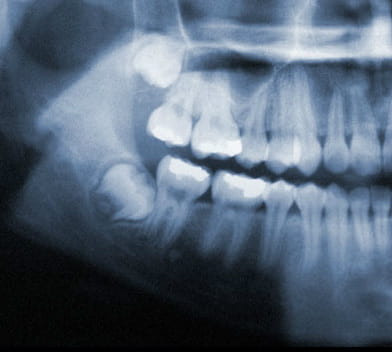

X-Ray of wisdom teeth

Wisdom teeth also known as third molars are the last teeth to erupt into the mouth. Wisdom teeth typically appear around a person's mid-twenties but can erupt much later. If wisdom teeth don't have enough space symptoms can occur. The wisdom teeth may only partially erupt or might not come through at all. Dentists designate wisdom teeth 'impacted' if they are wholly or partly blocked from eruption into the mouth. The tooth may lie at an angle and remain tipped against an adjacent tooth. Impacted wisdom teeth can cause problems like pain and swelling; The mouth could ache when stretched open wide or it may be difficult to open your mouth. Tenderness when chewing and biting may occur. Earaches may develop from the spread of pain in the mouth. Symptoms may be intermittent but can begin anytime without warning. If you are experiencing symptoms, it is best to get treatment 'usually removal' as soon as you can to avoid potentially expensive and painful complications.

Wisdom teeth generally begin to form in your pre-teen years. By late teen years, the crown of the wisdom teeth will begin to erupt through the gums if there is adequate room. By mid twenties, your wisdom teeth will either be able to fully erupt or will have become impacted. Early removal of wisdom teeth makes the procedure easier for the patient to tolerate and promotes faster healing after wards. By your early forties, the wisdom teeth roots have become fully anchored to the jawbone and if required to be extracted, will be much harder and will need more time to heal.